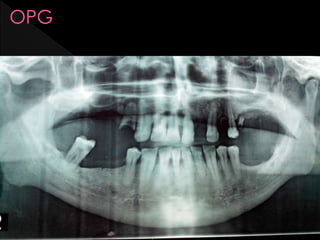

 Panoramic radiographic evaluation demonstrated

what appeared to be a normally formed mental

foramen.

 Panoramic radiographicevaluation demonstrated what appeared to be a normally formed mental foramen.  A diagnostic anesthetic injection of the mental nerve with one cubic centimeter of Citanest (Prilocaine HCl 4% without vasoconstrictor. Dentsply International, York, PA) alleviated all pain complaints with any movement of her face or lip. When the anesthetic effects were gone, her pain returned just as before the injection. A diagnosis of atypical trigeminal neuralgia of the mental nerve of unknown etiology was determined.